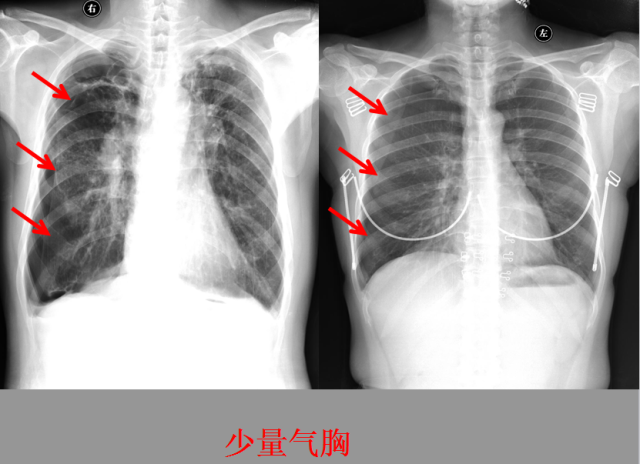

急胸症篇

急腹症篇